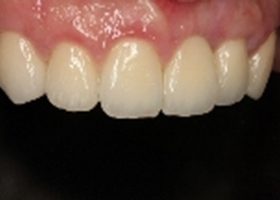

病患治療後,最終假牙完成照。